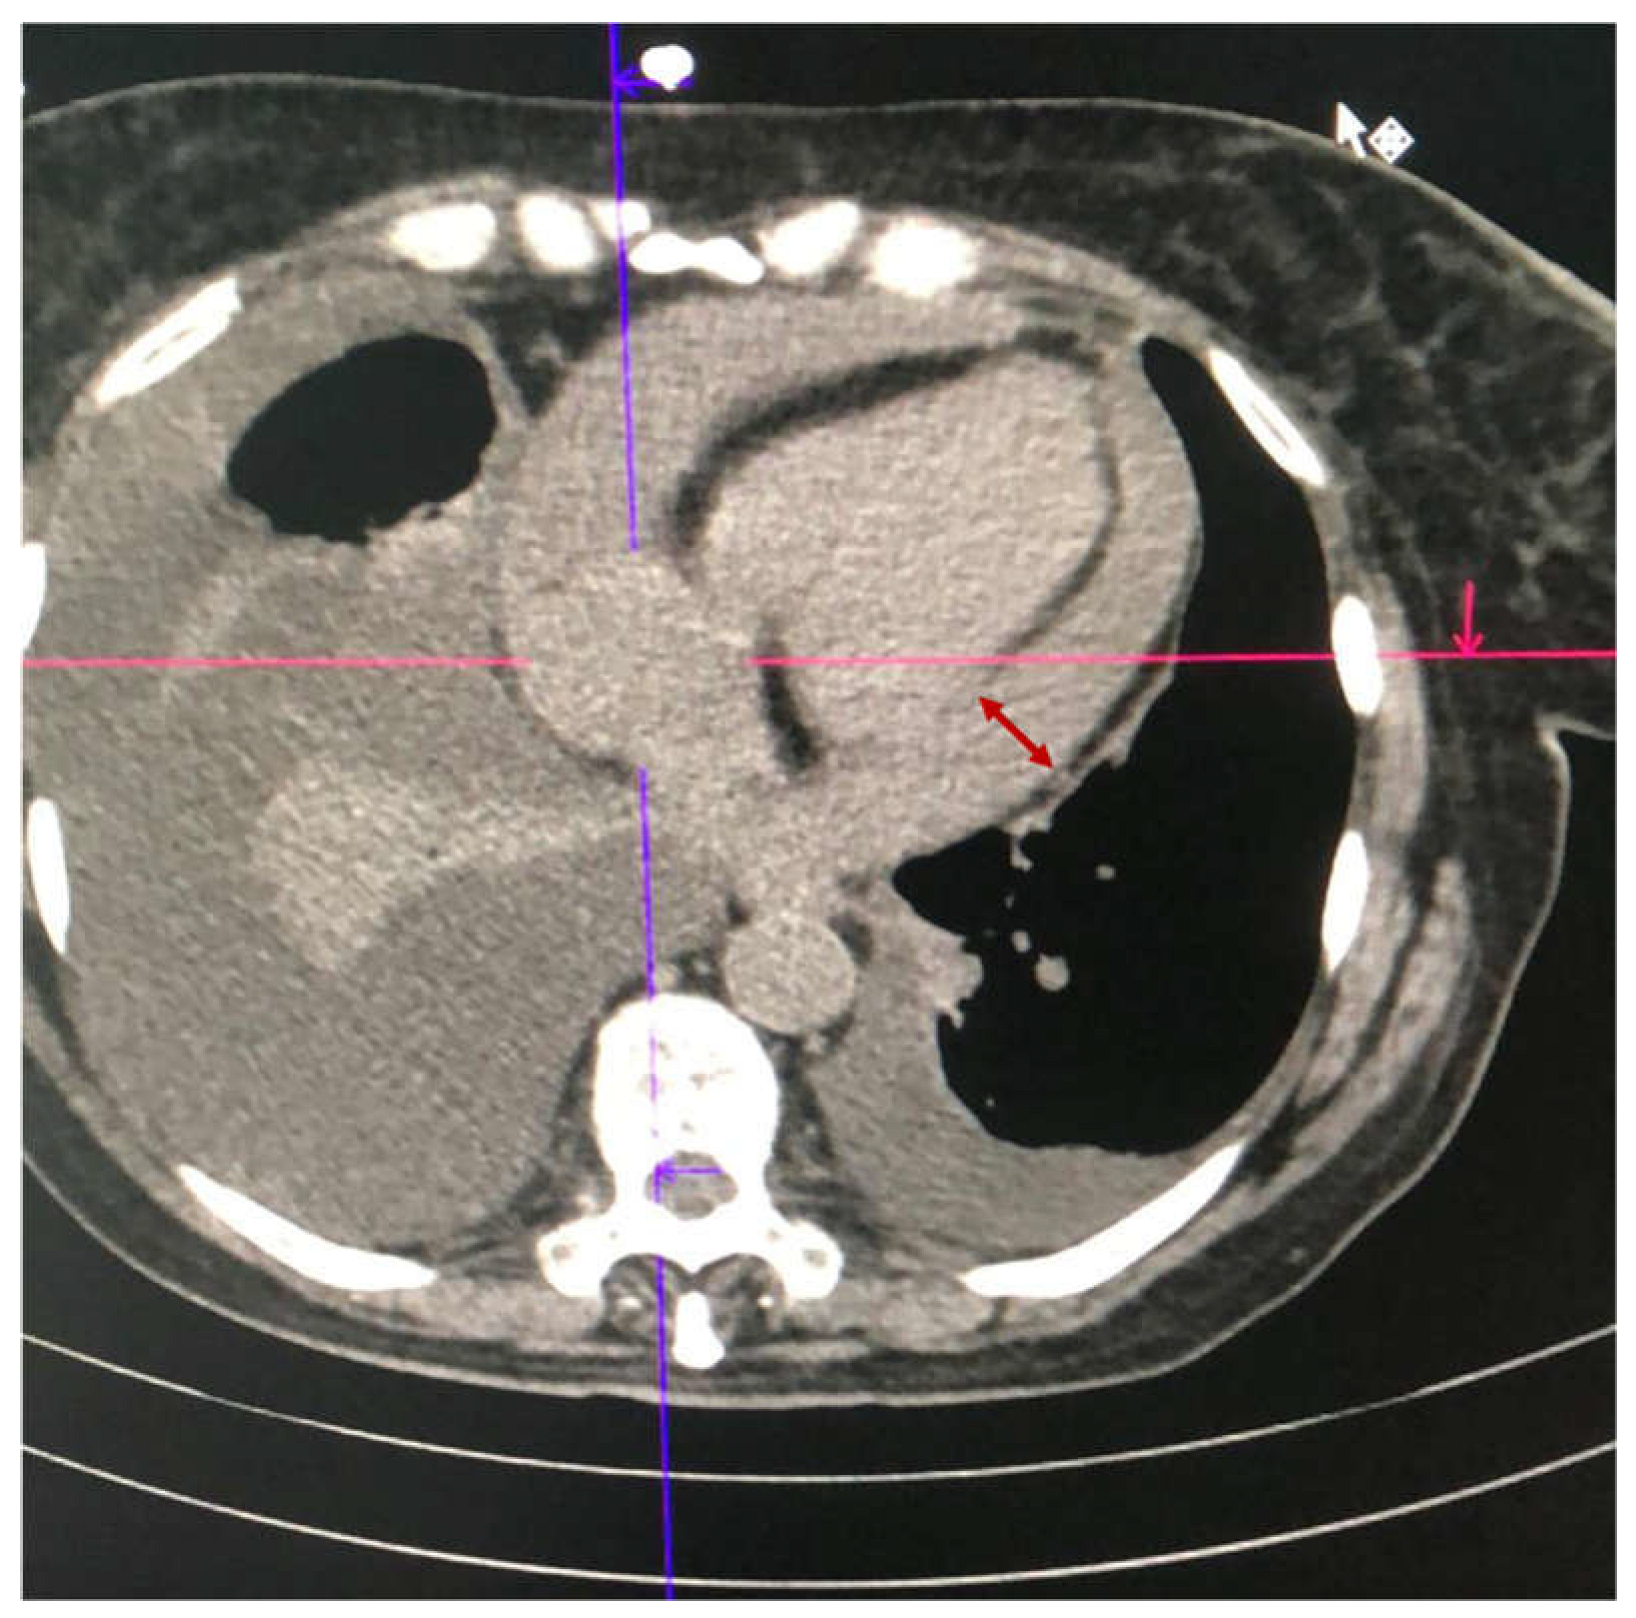

2.1. Case 1